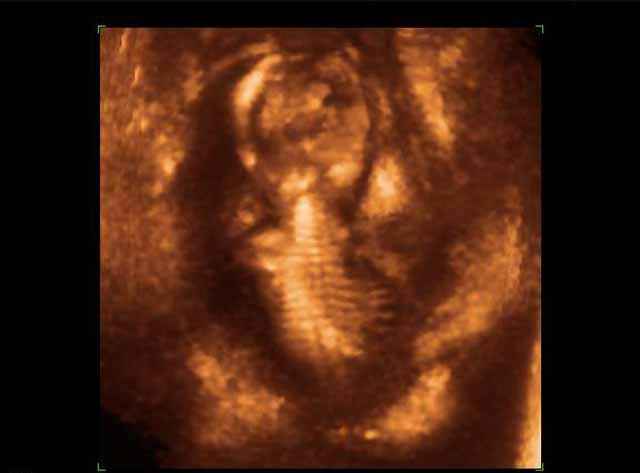

- صور لوجه الجنين في داخل الرحم

- صور جانبية لرأس الجنين

- صور لأعضاء الجنين

- صور لأطراف الجنين

- صور للجنين في المراحل الأولى من الحمل

- صور لتصرفات الجنين داخل الرحم

- صور للجنين في المراحل المتوسطة من الحمل

- صور طبية للحمل للأطباء